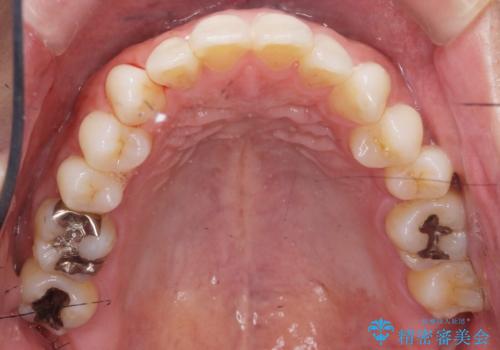

- 40代男性

- 寝ている間に歯ぎしりをしている気がするとの事で来院。

過去にナイトガードを使用したことがあったが穴が空いてしまったそうです。

ナイトガードを使用することによって歯がすり減る(寝ている時の歯ぎしりなど)事を防いでくれます。